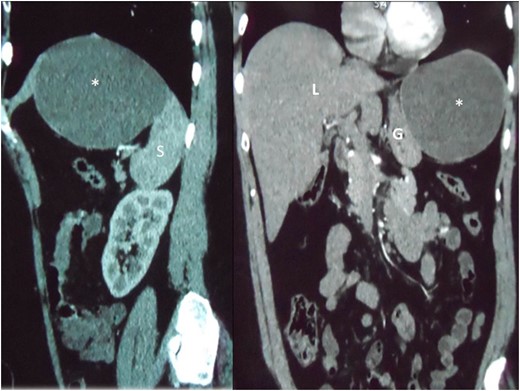

Reconstructed saggital and coronal views of a CT scan of the abdomen demonstrating the hepatic cyst (asterisk) in the sub-diaphragmatic space. The cyst is intimately related to the spleen (S), liver (L) and gastric body (G). The organ of origin cannot be determined from CT scans.